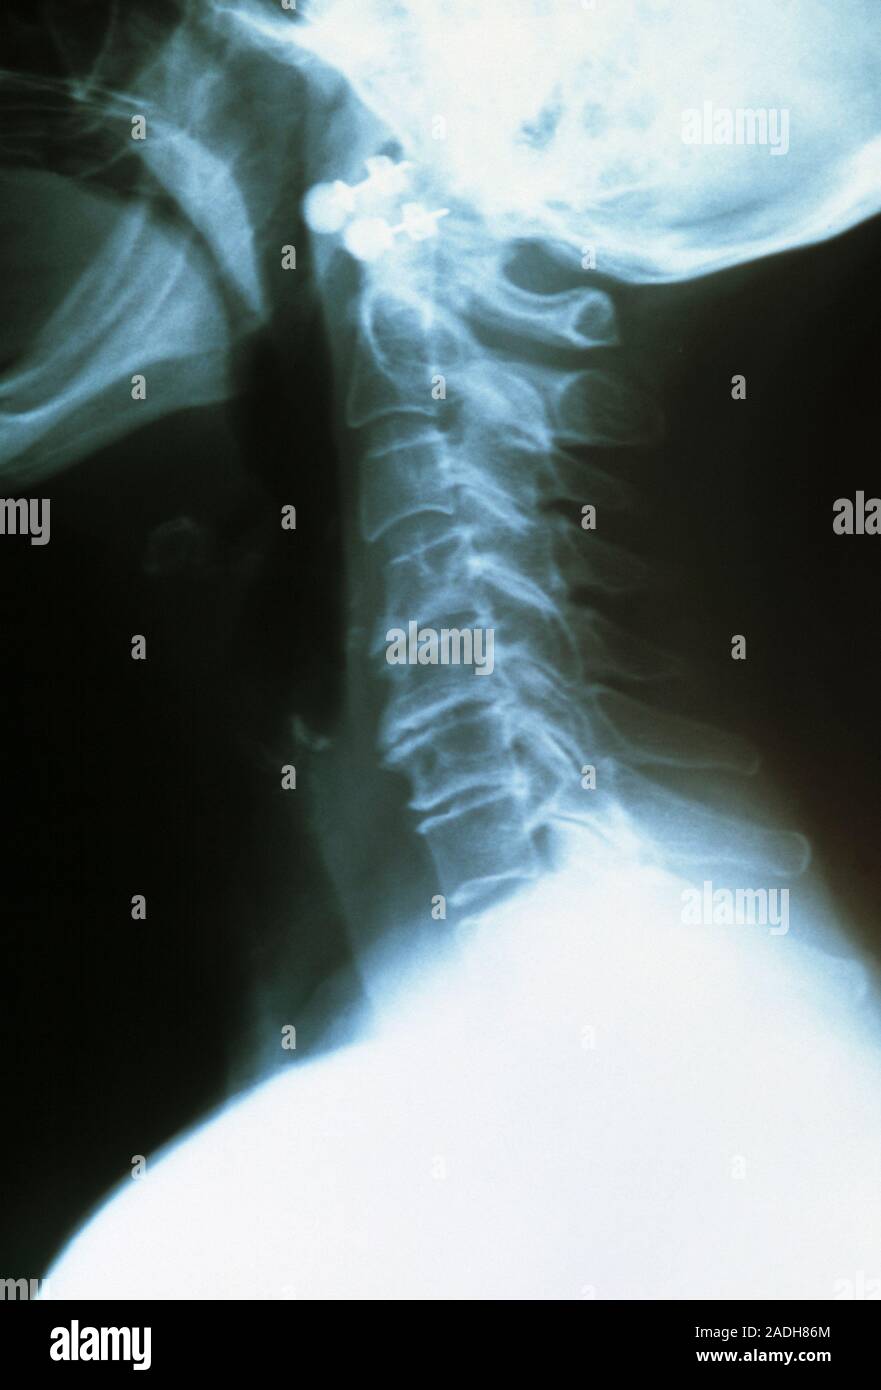

From www.alamy.com

Osteoarthritis of the neck. Coloured Xray of a side view of the neck Osteoarthritis In Neck And Head osteoarthritis occurs when the protective cartilage in a joint begins to break down and no longer facilitates smooth movement between bones, which can. Healthcare providers sometimes call it osteoarthritis of the neck or arthritis of the neck. spondylosis is when parts of your spine begin to wear out. osteoarthritis in the neck is the degeneration of joints,. Osteoarthritis In Neck And Head.